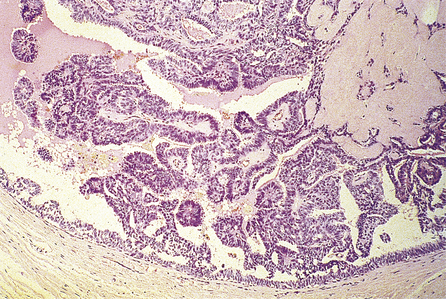

Lobular carcinoma in situ

Lobular carcinoma in situ occurs more frequently in pre-menopausal women, but can be found in biopsies taken to investigate mammographic (screening) abnormalities. A major problem is that it does not present as a palpable lump and is usually found in biopsies removed for other reasons. A further important clinical feature is that it is often multifocal within the one breast and is frequently bilateral. Not surprisingly, there are no specific radiological or macroscopic features.

Histologically, the changes are found in the acini—hence the term ‘lobular’—although they may extend into extralobular ducts and replace ductal epithelium (Fig. 18.19). Within the acini, the normal cells are replaced by relatively uniform cells with clear cytoplasm that appear loose and non-cohesive. The overall size of the acini increases, but the lobular shape is retained. Unlike the situation in ductal carcinoma in situ, necrosis is unusual.

image

Fig. 18.19 Lobular carcinoma in situ. A breast lobule in which the acini are expanded. There is complete loss of the lumen and of the two-cell layer.